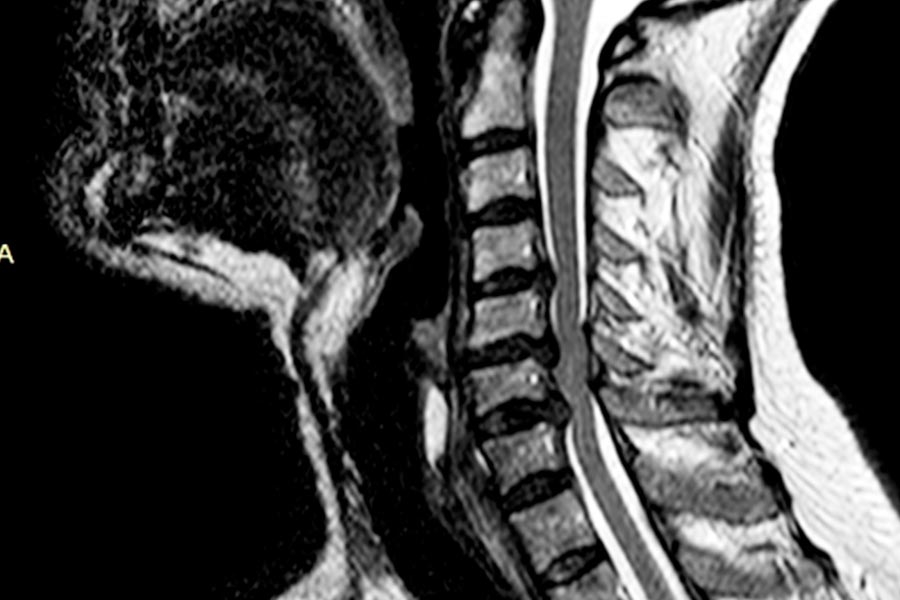

Caso clínico: endoscopia de columna multinivel L4L5 y L5S1

Los síntomas que presentaba el paciente eran dolores acentuados en las piernas, claudicación a la marcha y calambres y hormigueos en las piernas.

Durante la intervención quirúrgica, se abordarán los dos niveles mediante la técnica de endoscopia de columna.